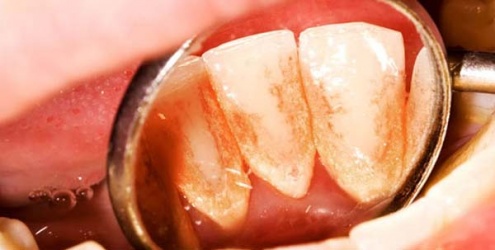

وهو من الأمراض الأكثر شيوعاً على الرغم من العناية بالفم والأسنان، إلا أن بعض الأشخاص يمتلكون لثة حساسة بحيث تتجمع طبقة من البلاك عند تجويف الأسنان ولا تستطيع الفرشاة الحصول عليها. ومع الوقت تصبح الطبقة أكبر وتحدث التسلخات والجروح بمنطقة اللثة، وبعدها تنمو البكتيريا بسبب وجود اللعاب والجراثيم فتسبب التهاب مع نزيف في اللثة المستمر بسبب تلك البكتيريا، ومن أسباب نزيف اللثة :

• التهاب البكتيري للأسنان وبالتالي يكون طبقة لزجة يميل لونها إلى الأبيض وتسمى المادة (الصفائح الدموية) وتتكيف البكتيريا على هذه المنطقة وتؤدي إلى تهيج اللثة، وبالتالي تصبح منتفخة ومتورمة بين الأسنان، ويصل هذا الالتهاب إلى منبت السن ثم إلى العصب ومما يؤدي إلى التهاب العصب السني وبالتالي فقدان السن.